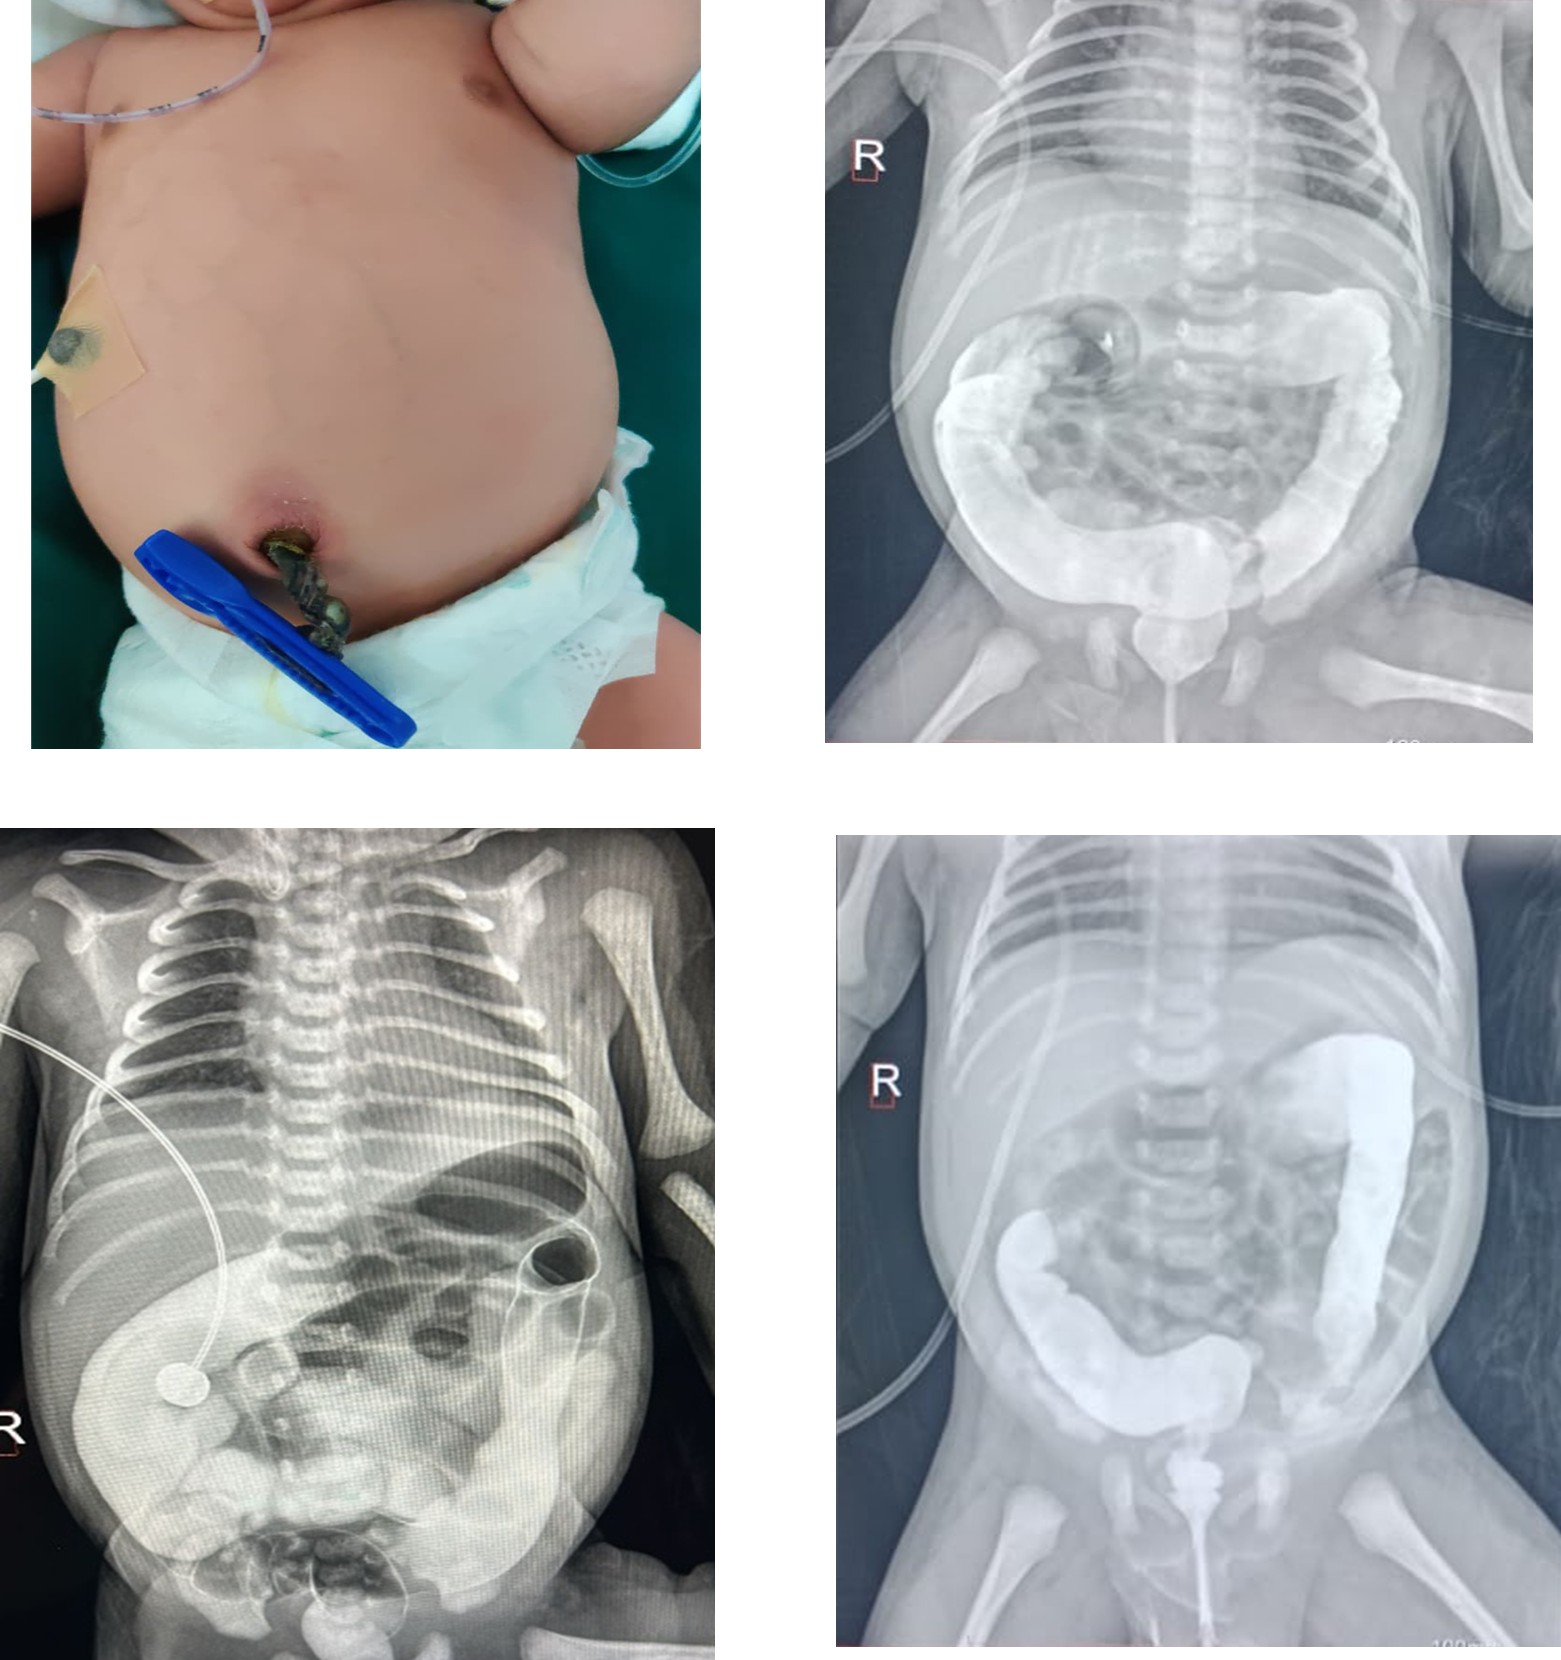

4. Midgut Malrotation (Surgical Condition)

As feeds advanced, the baby developed tachypnea and bile-stained gastric aspirates. From 30 hours, feeds were withheld (NPO). Sepsis markers were elevated (CRP 4.1 mg/dL) and antibiotics were escalated, but bilious aspirates persisted. Abdominal ultrasonography suggested malrotation, and a contrast study confirmed obstruction. On day 4 of life, emergency exploratory laparotomy was performed. Midgut malrotation was identified; de rotation and Ladd’s procedure were successfully completed. Postoperatively, the baby remained NPO for 3 days and received glucose infusion and amino acid nutrition. Enteral feeds were restarted on postoperative day 3 and advanced gradually to full feeds by day 12.

Management and Nutritional Support

Ladd’s procedure remains the definitive treatment for midgut malrotation and is most effective when performed before the onset of volvulus and bowel ischemia. Early surgical intervention in this neonate resulted in preservation of bowel integrity and favourable postoperative recovery. Postoperative nutritional management with glucose infusion and amino acid supplementation played a vital role in maintaining metabolic stability and promoting healing until enteral feeds could be safely resumed. Gradual feed advancement minimized the risk of feed intolerance and necrotizing enterocolitis.